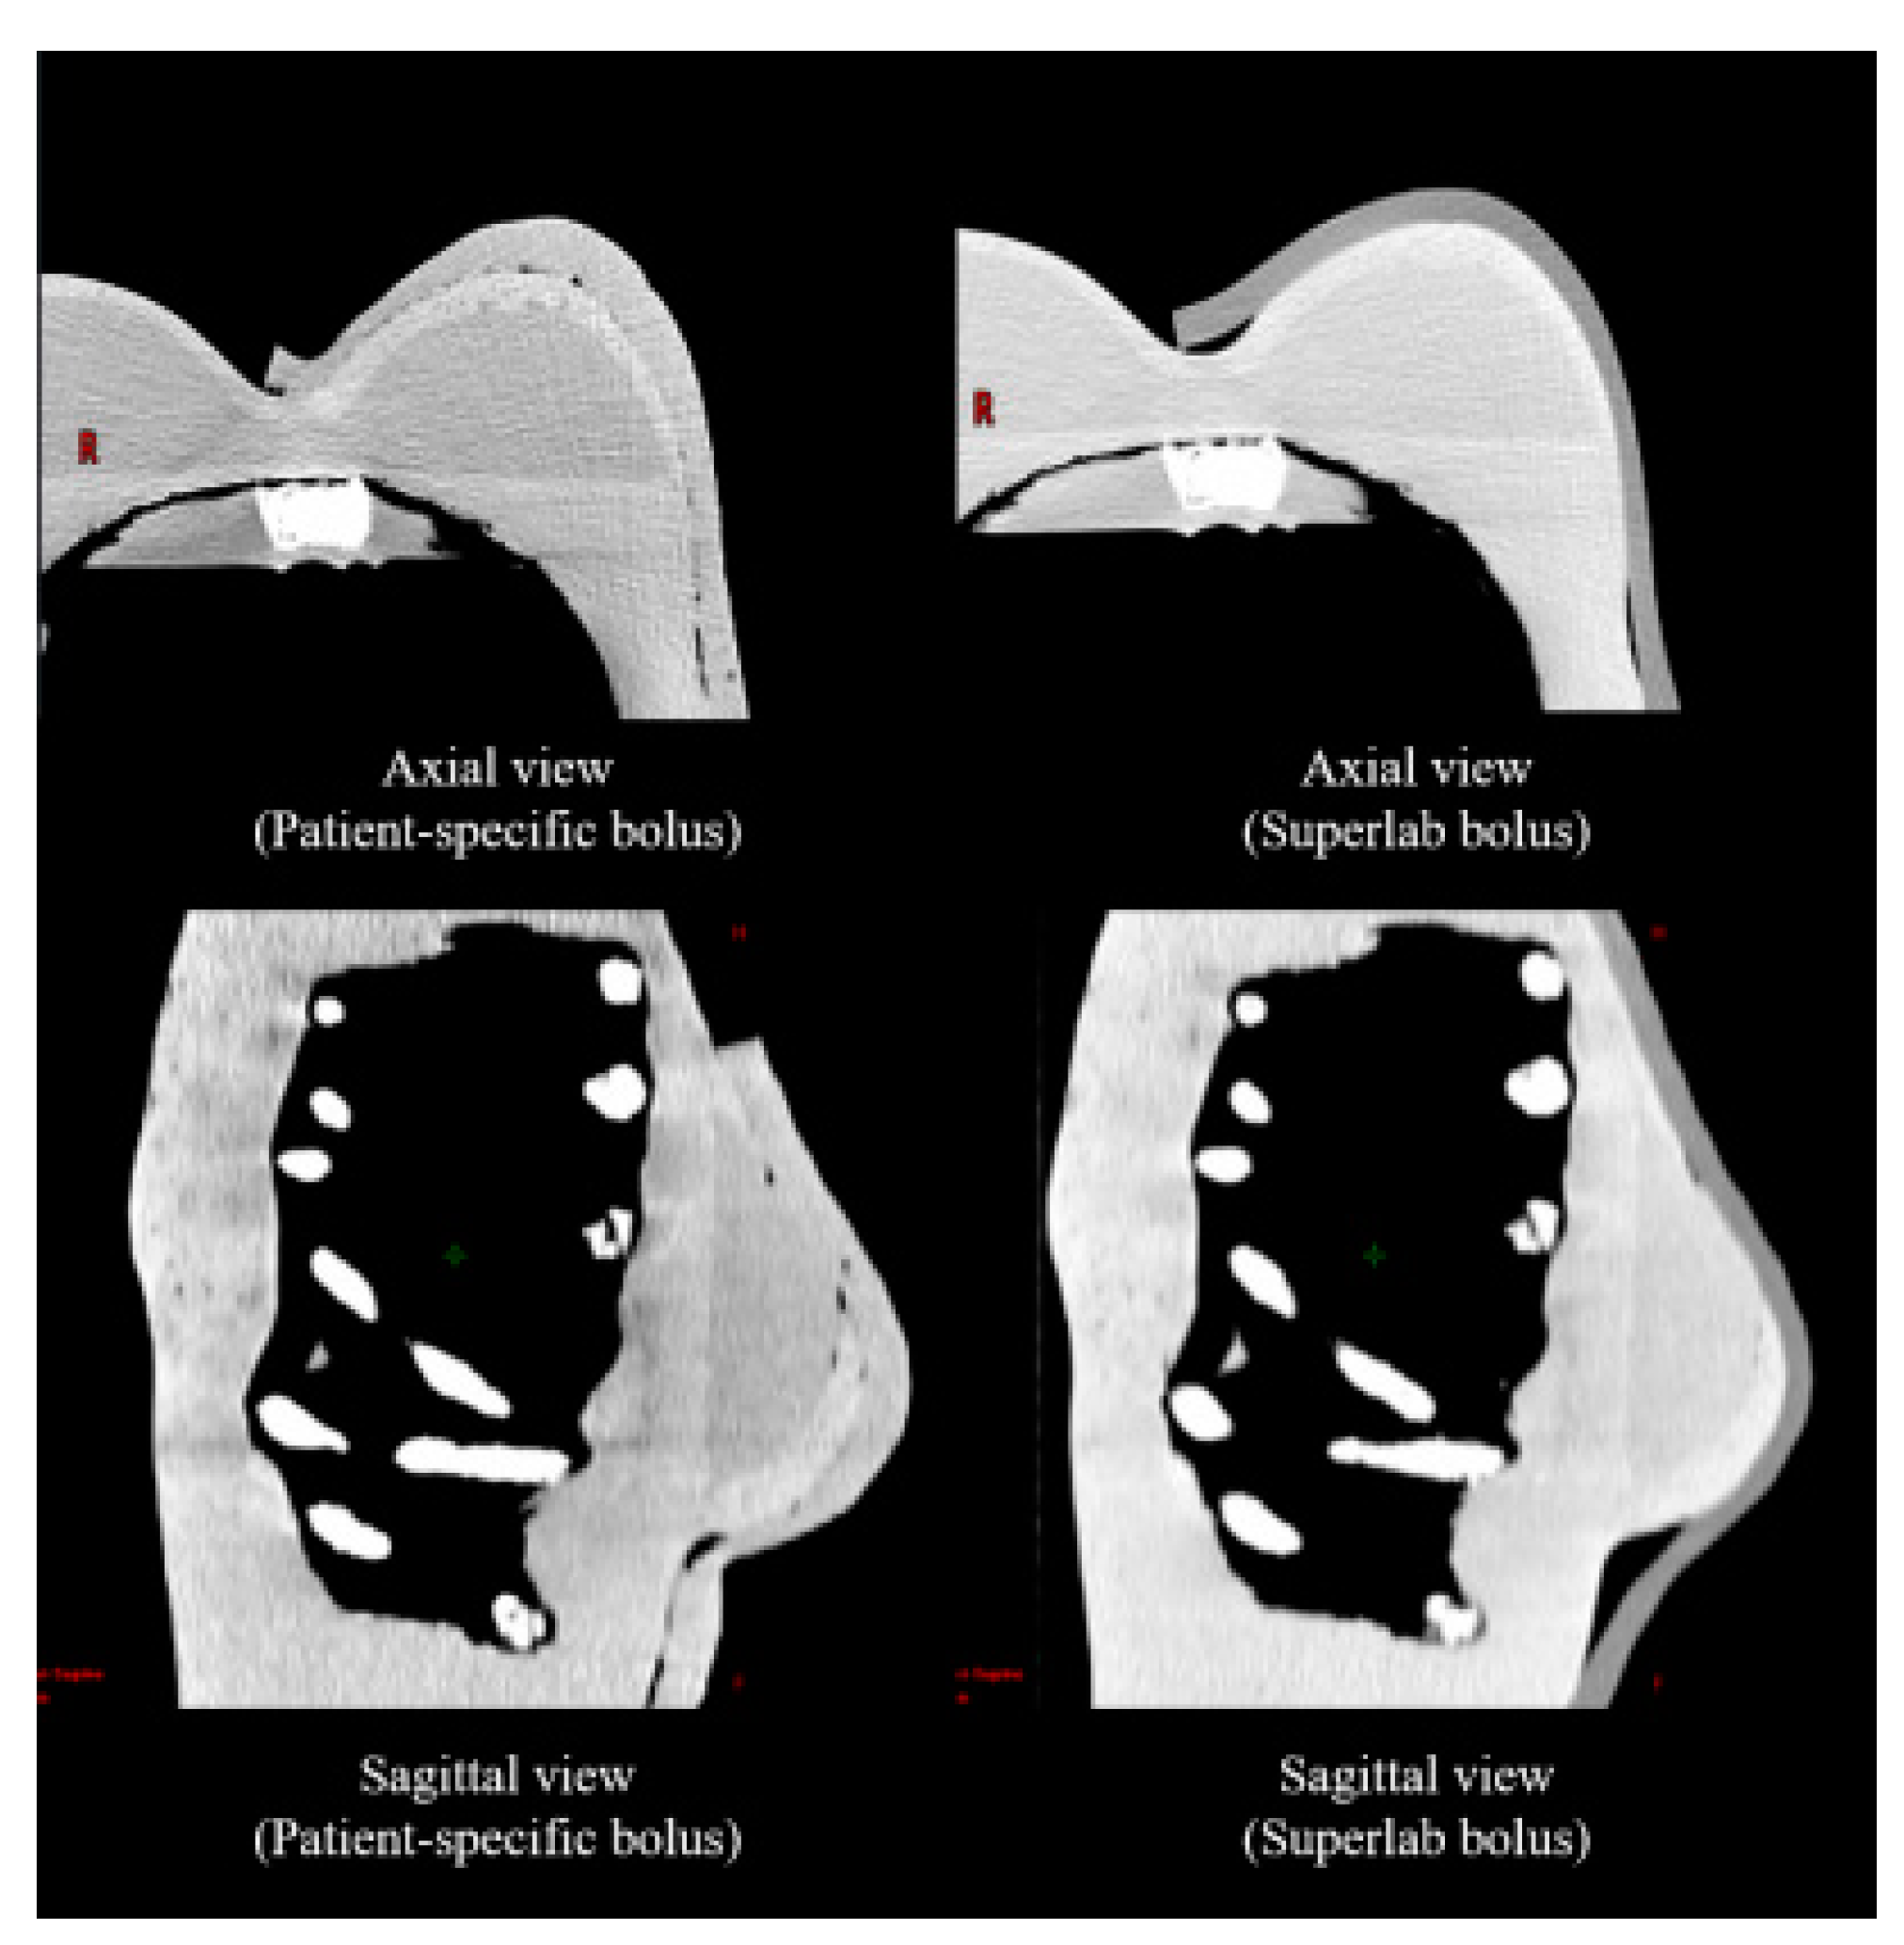

2.2. Air-Gap Quantification

3.1. Air Gap Quantification